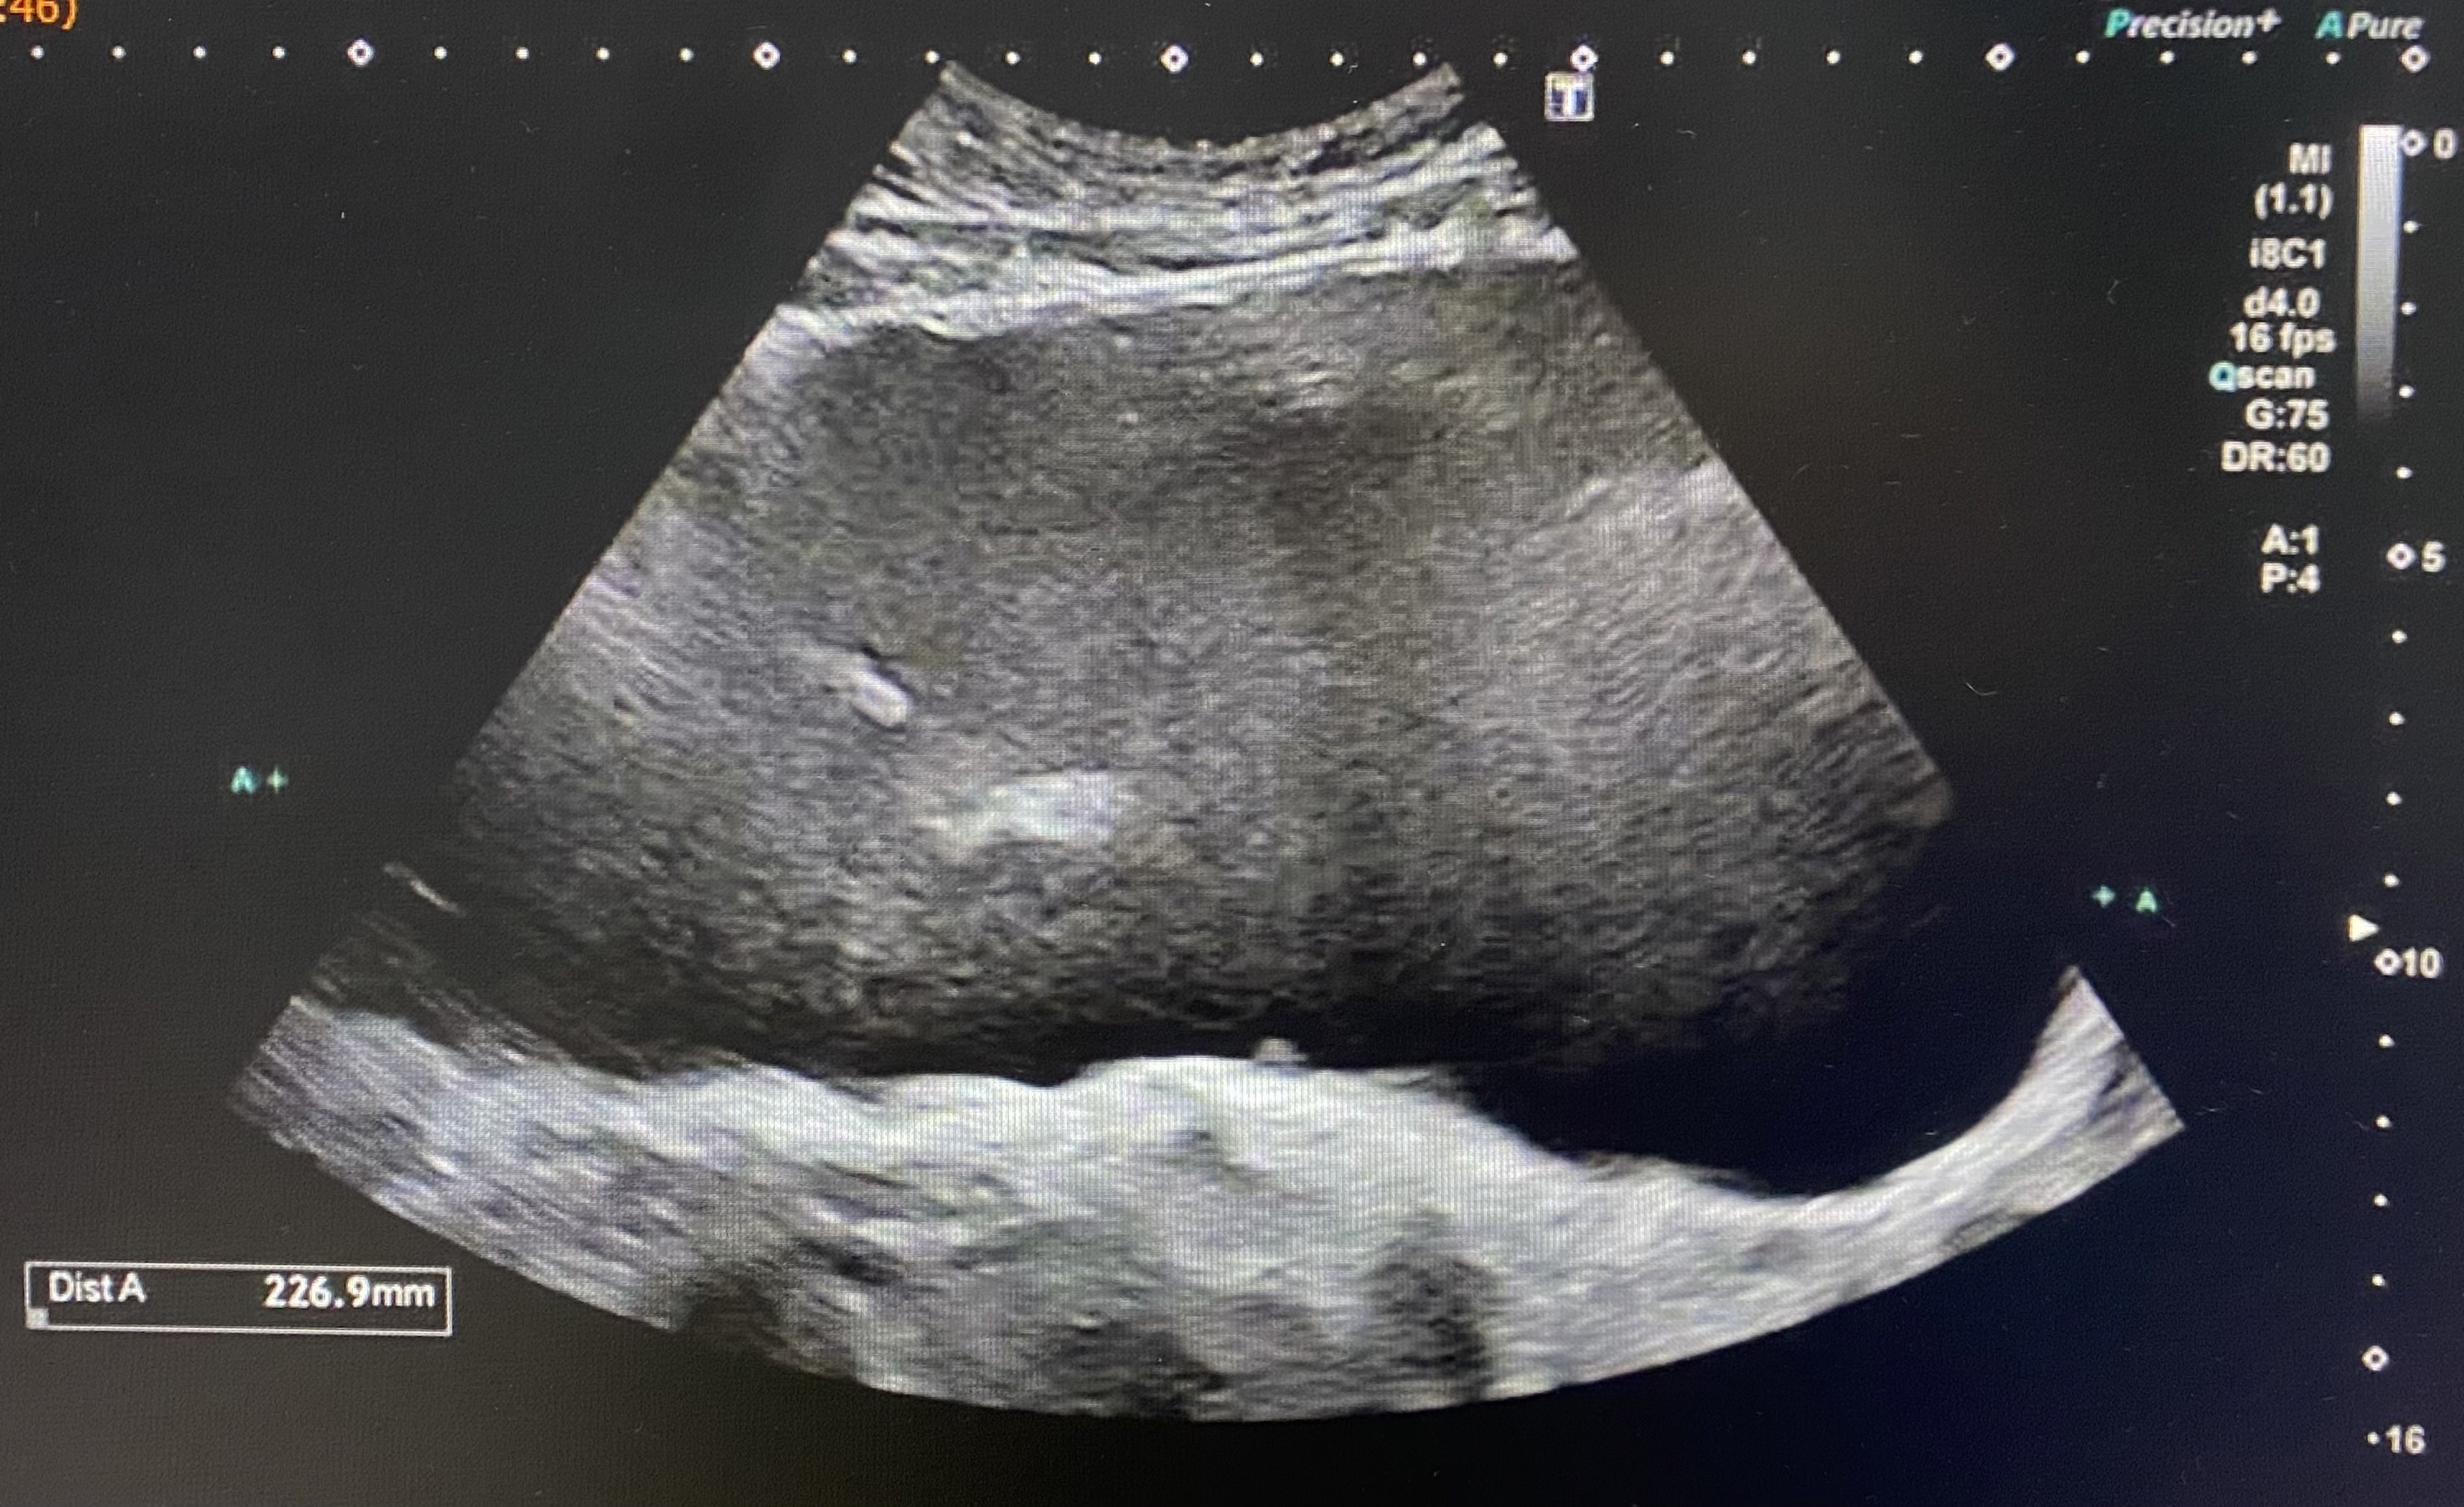

El paciente fue derivado a urgencias hospitalarias para valoración. Se realizó una ecografía a su llegada, observando una marcada distensión vesical (imagen 1) con dilatación pielocalicial y ureteral bilateral, con parénquima renal conservado (imagen 2).